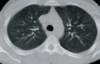

22

Permite diferenciar las estructuras mediastínicas entre sí, pero el parénquima pulmonar aparece todo negro, sin apenas trama broncovascular.